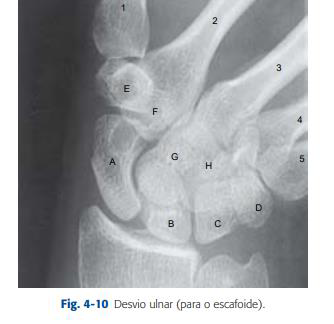

A sequência F, G, H é representada, respectivamente, pelos seguintes ossos:

A sequência B, C e D é representada, respectivamente, pelos seguintes ossos: